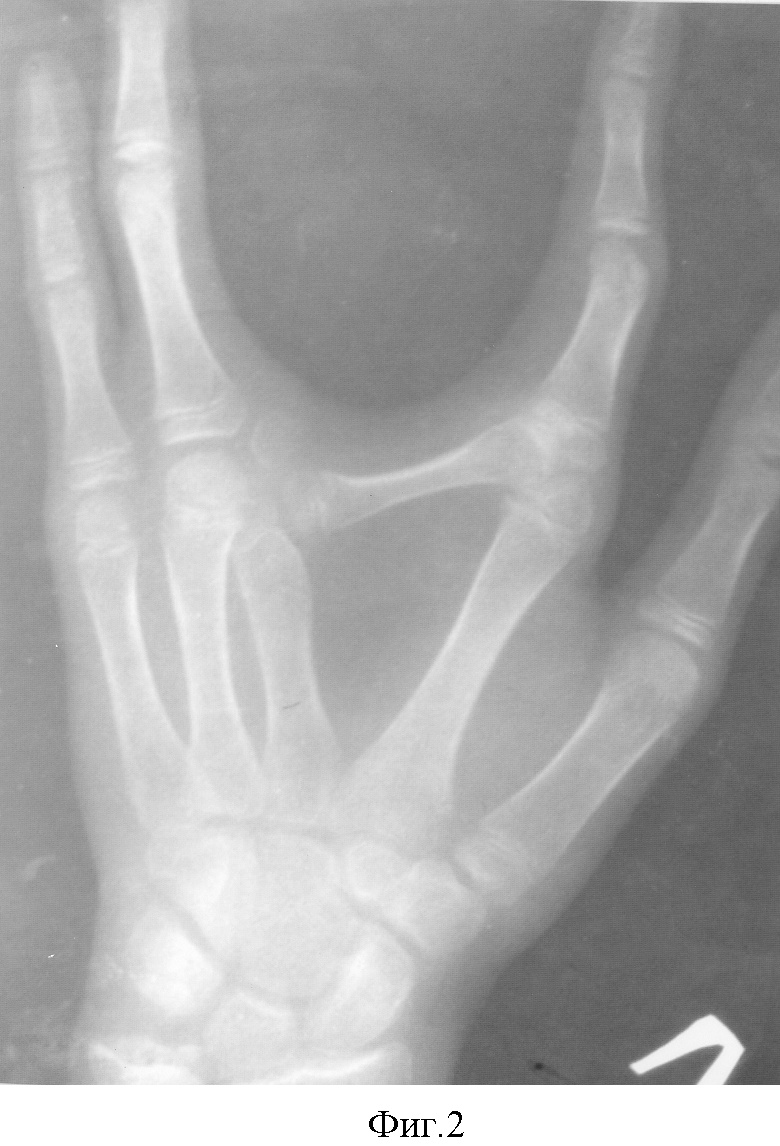

Больной И-В 1988 г.р., история болезни №2382. Из анамнеза: страдает врожденным, атипичной формы, расщеплением левой кисти, который приносит пациенту функциональные неудобства и дискомфорт при общении с окружающими (фиг.1,2).

29.05.03 г. в отделении хирургии кисти НИЦТ «ВТО» выполнена операция по вышеописанной методике: ракетообразный разрез по расщелине кисти, с тыльного доступа вычленена головка дополнительной поперечной кости со второго пястно-фалангового сочленения, смещены навстречу друг другу вторая и третья пястные кости до достижения анатомической ширины кисти. Приложив дополнительную поперечную кость с тылу второй пястной кости, определена необходимая длина этой кости, подлежащая удалению. После этого удален лучевой конец дополнительной поперечной кости. Под головкой поперечно перепилена вторая пястная кость, и второй палец вместе с головкой пястной кости ротирован до функциональной позиции второго пальца по отношению к кисти. Достигнутое положение костей фиксировано спицами (фиг.3). Послойные швы на рану. Спиртовая повязка. Гипс до снятия кожных швов. Заживление раны первичным натяжением. Спицы удалены через 2 мес. Контрольный осмотр через 1,5 года. Достигнута хорошая анатомическая структура и улучшилась функция кисти (фиг.4,5).